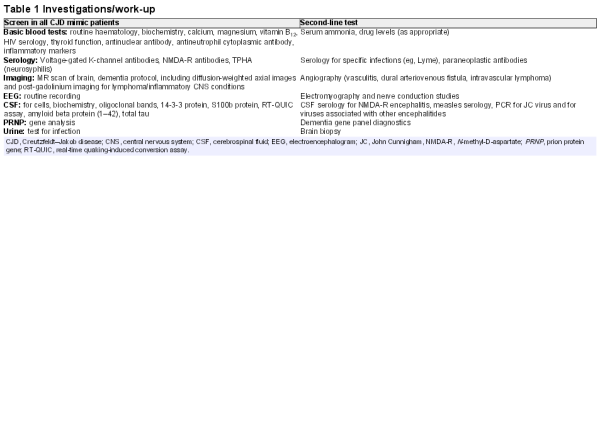

The first symptoms of sporadic CJD are usually non-specific: headache, malaise, cough, dizziness and change in personality, mood or memory. The first more CJD-specific symptoms are diverse and lead to distinct initial differentials (figure 1). In half of the cases, the more typical picture of CJD is present on exploring the history further or reveals itself during examination or shortly after an initial assessment. In its classical presentation (figure 1), the clinical syndrome of CJD comprises an RPD (widespread cognitive domains: memory, dysexecutive, behaviour disturbance, abnormalities of calculation and spelling and dysphasia) associated with cerebellar ataxia, myoclonus, pyramidal and extrapyramidal motor signs and often evidence of a disorder of higher visual functions. Aside from rapid forms of common neurodegenerative diseases, the main differentials are limbic, corticosteroid-responsive or infective encephalitis, paraneoplastic conditions, Wernicke’s encephalopathy, neurosarcoidosis, hypothyroidism, non-convulsive status epilepticus, hypoxic encephalopathy, a toxic/metabolic syndrome or a functional disorder.

Figure 1

Creutzfeldt-Jakob disease (CJD) clinical features and progression. The boxes describe clinical variants of CJD. The width of each arrow relates to the proportion of cases with the presentation. Patients with CJD become more similar over time, and almost all enter a phase of ‘akinetic mutism’ before death.

Atypical presentations cause more difficulty, including pure cognitive presentations (~15%) that might be mistaken for rapid forms of Alzheimer’s disease, frontotemporal dementia or dementia with Lewy bodies; ataxic presentations (~10%) are often associated with acquired CJD and might be mistaken for disorders of the cerebellum and its brainstem connections, including vascular, neoplastic, paraneoplastic or inflammatory conditions. The visual presentation or Heidenhain variant (~5%) is particularly distressing for patients with hemianopia or scotoma, misperceptions, hallucinations, distortions and palinopsia. Progression tends to be rapid, even relative to other presentations of CJD. The condition often presents to ophthalmologists or optometrists as an ocular disorder, for example, suspected cataract.Psychiatric presentations (~5%) also occur; thus, in variant CJD, depression and personality change are common early in the evolution of the disease, while paranoia, visual hallucinations and aggression occasionally occur during the initial phase of the disease in sporadic CJD, suggesting a primary psychiatric diagnosis of psychosis or depression. Very rare presentations include those that mimic a stroke (~2%) or corticobasal syndrome (~2%). The thalamic presentation (~2%) includes sleep disturbance and distal pain and may include abnormalities of the autonomic nervous system: palpitations, temperature dysregulation, hypertension or postural hypotension. This presentation is well known as fatal familial insomnia and is typically associated with the inherited prion disease caused by the D178N missense mutation in PRNP, usually linked to a methionine allele at polymorphic codon 129; however, there have been cases without this or any gene mutation.